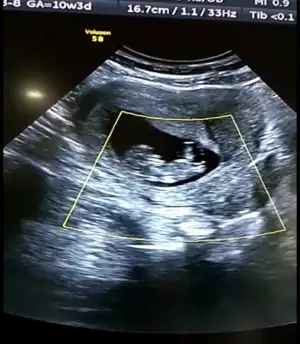

Benim icin de bir tahminde bulunabilir misiniz acaba? :) 4 li resimde sol üsttekine bacakları varmışVarsa 11 12 13 hafta usg ttahmin ederim![]()

Canım hiç net değil usg ler 13 hafta olursa tekrar usg paylaşın şimdilik emin değilim sanki kız ama değilimBenim icin de bir tahminde bulunabilir misiniz acaba? :) 4 li resimde sol üsttekine bacakları varmış

Çok teşekkür ederim 13. Haftada tekrar paylaşırımCanım hiç net değil usg ler 13 hafta olursa tekrar usg paylaşın şimdilik emin değilim sanki kız ama değilim![]()

Benim icin de bir tahminde bulunabilir misiniz acaba? :) 4 li resimde sol üsttekine bacakları varmış

Bana da kız gibi geldi canım